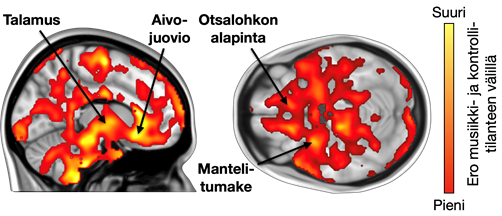

Tutkimuksessa mitattiin opioidien vapautumista aivoissa positroniemissiotomografialla (PET) samalla, kun osallistujat kuuntelivat omaa lempimusiikkiaan. Lisäksi toiminnallista magneettikuvantamista käytettiin selvittämään, miten opioidireseptorien tiheys vaikuttaa aivojen aktivaatioon musiikkia kuunnellessa.

Tulokset osoittavat, että lempimusiikki vaikutti opioidien vapautumiseen useilla aivojen alueilla, jotka on liitetty mielihyvä kokemukseen. Opioidien vapautuminen oli myös yhteydessä siihen, kuinka usein osallistujat kokivat nautinnollisia vilunväristyksiä musiikkia kuunnellessaan. Lisäksi yksilölliset erot opioidireseptorien määrässä olivat yhteydessä aivojen aktivoitumiseen musiikin kuuntelun aikana: mitä enemmän opioidireseptoreita osallistujilla oli, sitä voimakkaammin aivot reagoivat musiikkiin magneettikuvantamisessa.